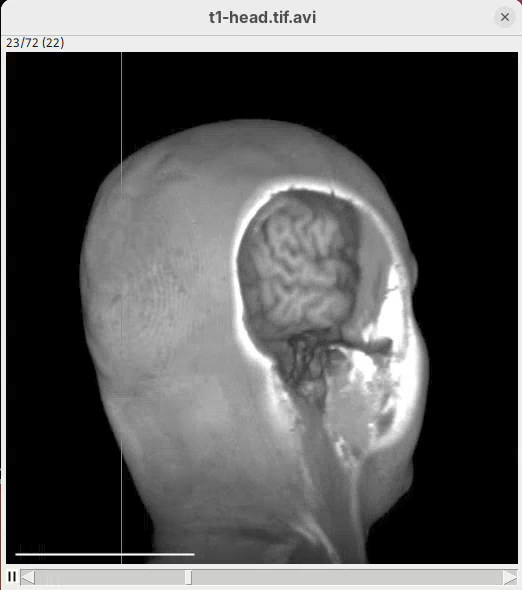

Cropping

Another useful 3Dscript option is the ability to crop the bounding box to show the inside of the sample. We can do it in the XYZ directions or in the near/far axis, defined from the user point of view.

- Set the Z range minimum value to

60(you can also drag the slider) to slice the sample through the Z axis.

- Now rotate the sample to see the cropped region from other angles.

- Set the Y range

minto125and rotate around.

- Finally, reset the position and cropping parameters and set the Near/Far minimum to

0and move the sample around to see the dynamic reslice of the sample with this cropping parameter.

- Reset transformations and cropping parameters.